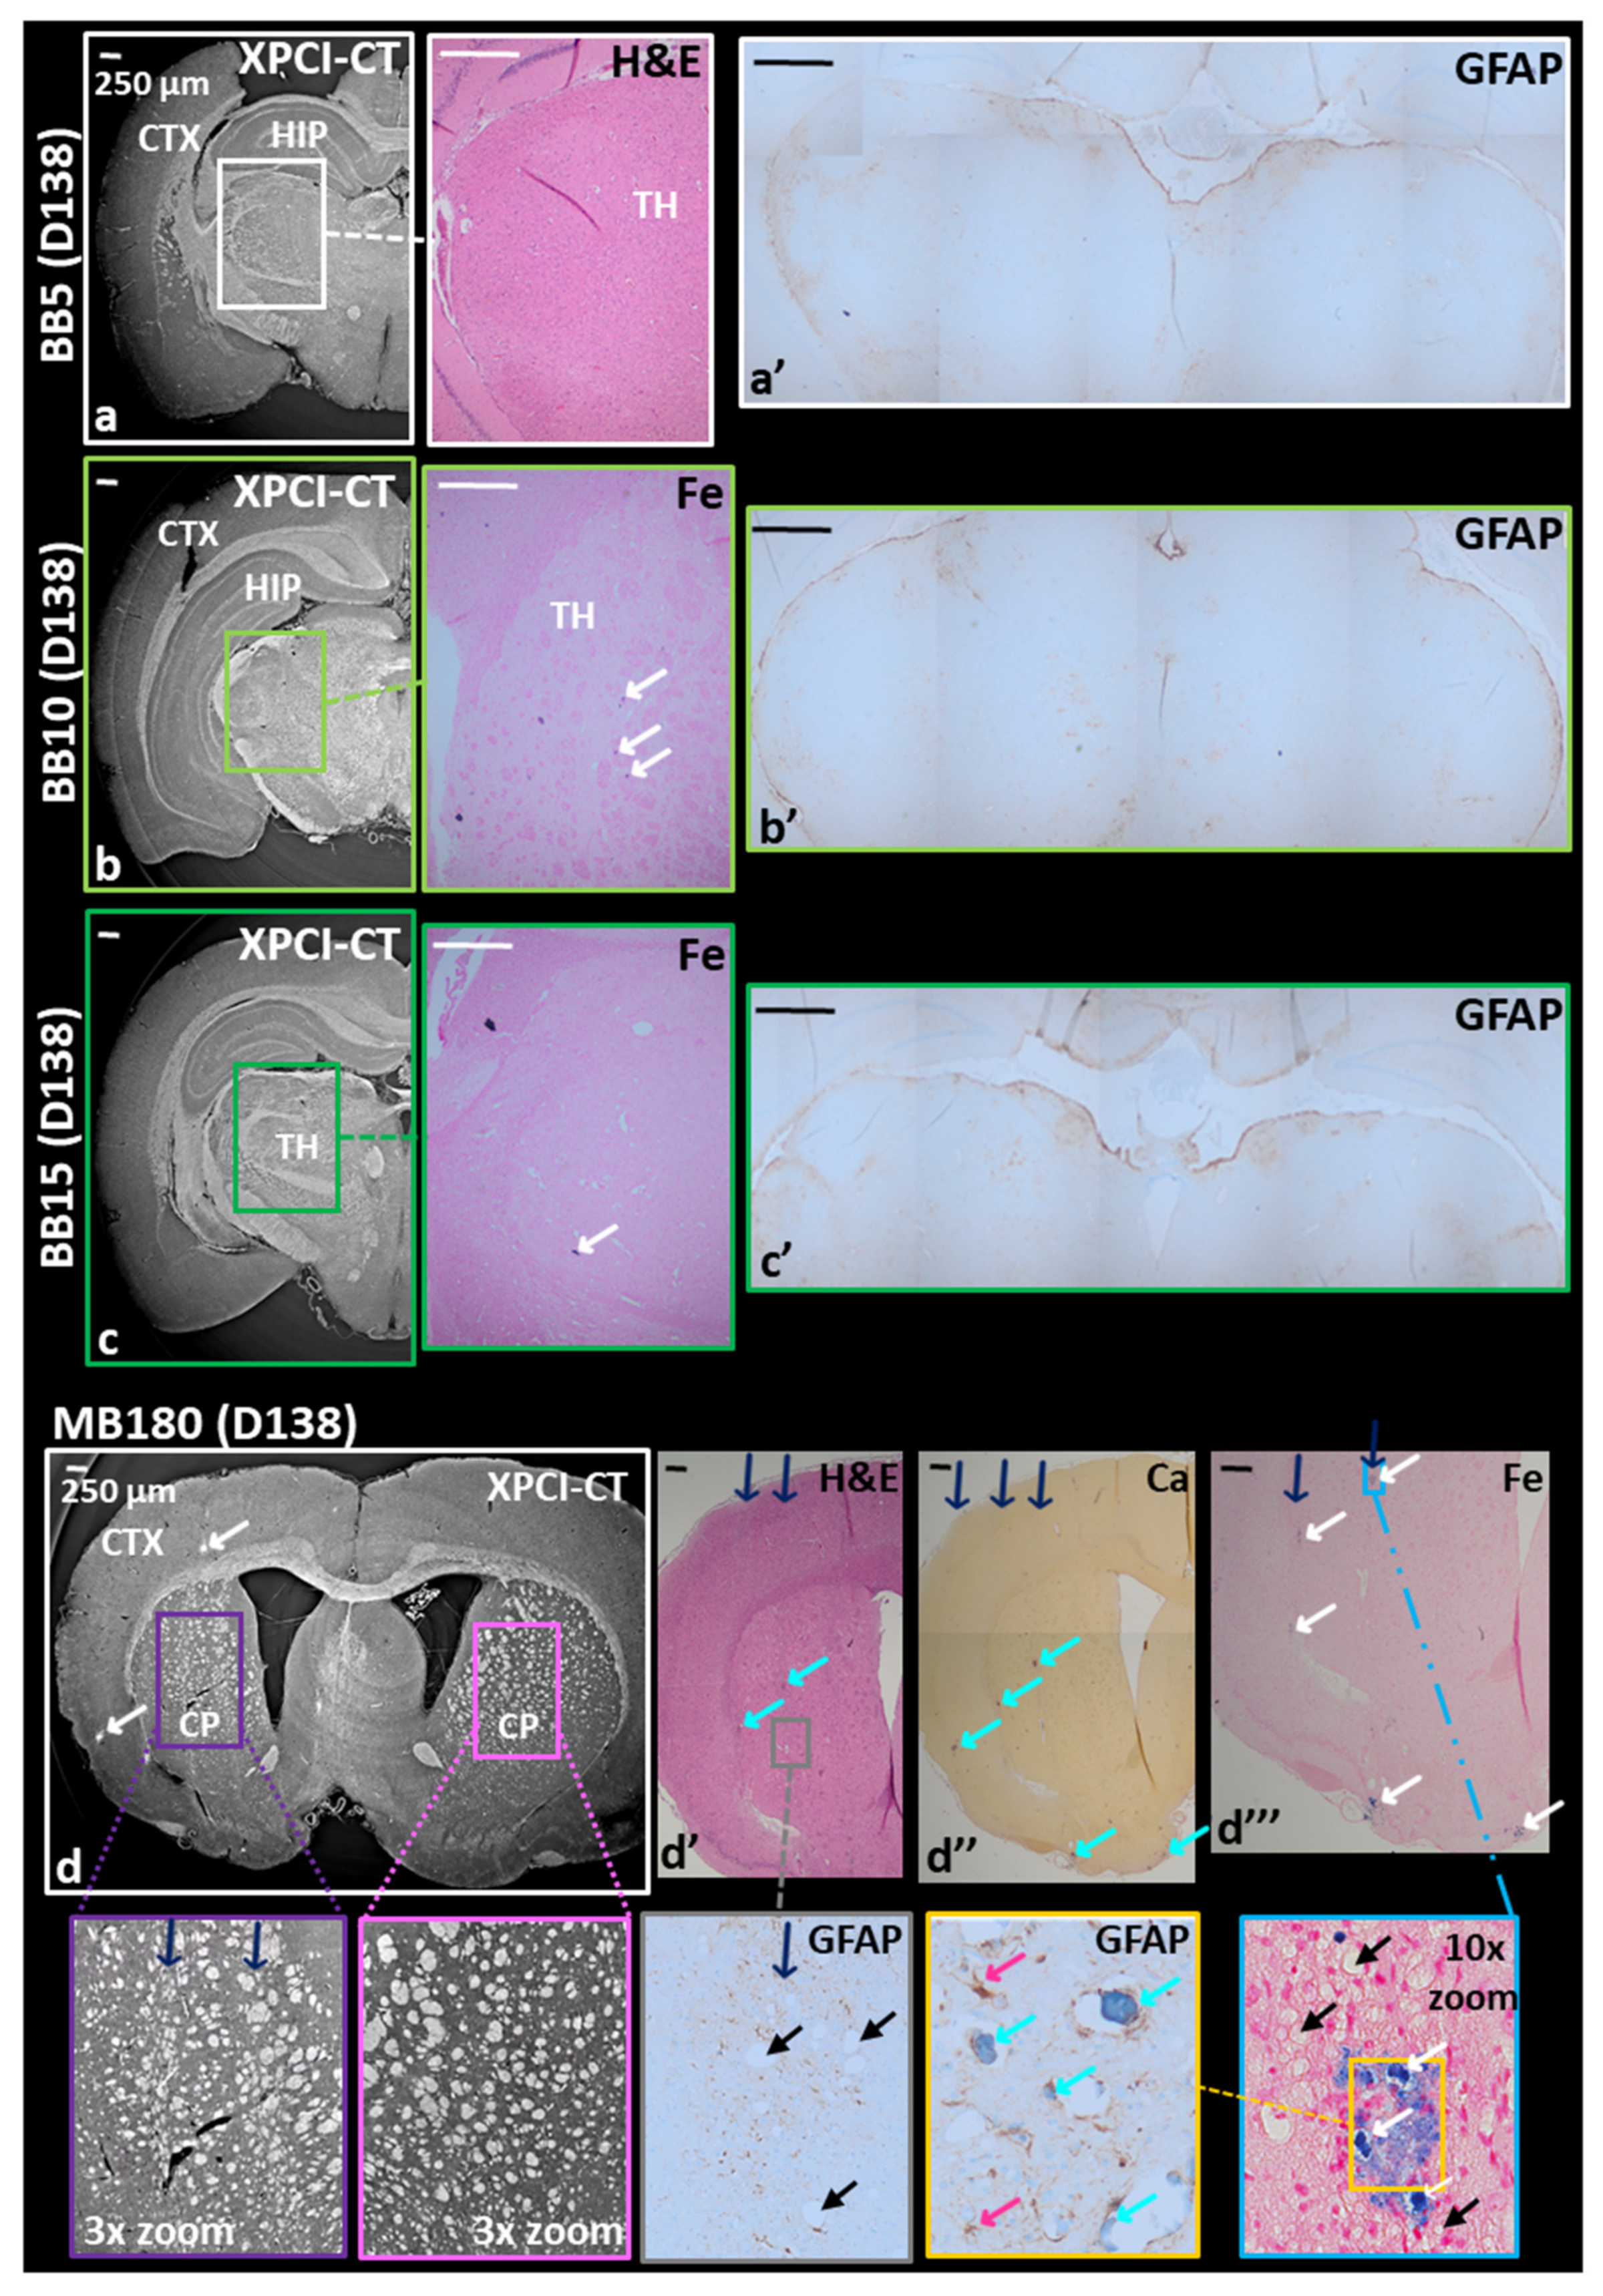

3.1. Radio-Induced Effects on Healthy Treated Rat Brains

3.2. Effects of Spatially Fractionated Radiotherapy on Glioblastoma-Bearing Animals

4.1. Effects of Treated Healthy Rat Brains

4.2. Effects on GBM-Bearing Rat Brains